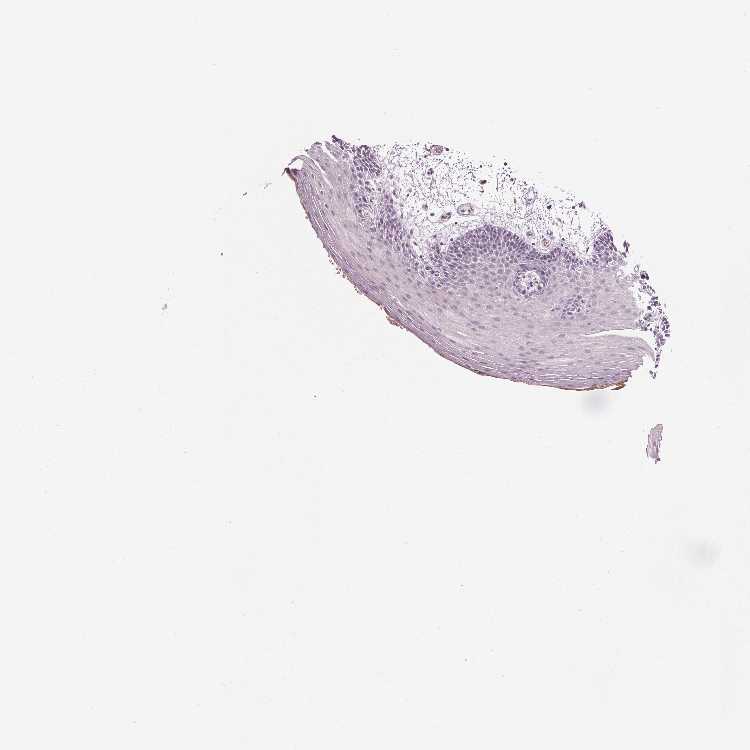

TISSUE PRIMARY DATA ORAL MUCOSA Show tissue menu

ORAL MUCOSA - Antibody stainingi

Antibody staining in the annotated cell types in the current human tissue is reported as not detected, low, medium, or high, based on conventional immunohistochemistry profiling in selected tissues. This score is based on the combination of the staining intensity and fraction of stained cells.

Each image is clickable and will lead to virtual microscopy that enables deeper exploration of all samples and also displays staining intensity scores, fraction scores and subcellular localization as well as patient and tissue information for each sample.

Antibody HPA039486Antibody HPA048186

Squamous epithelial cells Not detectedNot detected